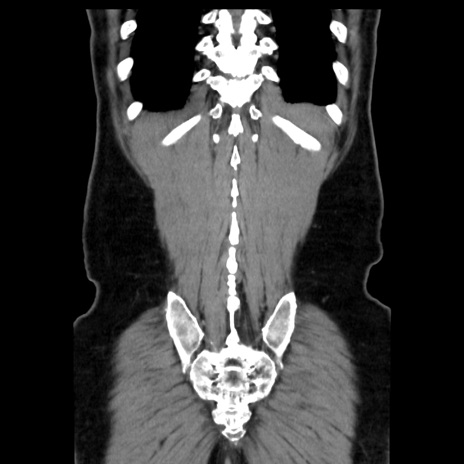

症例16(冠状断像)

【症例】 70歳代男性

【主訴】 腹痛、嘔吐

【現病歴】 約1ヶ月前より間欠的に腹痛と嘔吐あり、当院消化器内科を受診したところCTで多発する肝臓のLDAを指摘され、精査中であった。以降は消化器症状は安定していたが、2日前より嘔気と腹痛があり、同日より排便・排ガスが消失した。改善認めず、 本日、救急外来を受診した。

【既往歴】 大腸ポリープ切除後。

【身体所見】意識清明・会話良好、BT 36.3℃、BP 127/80mmHg、 P 80bpm、腹部:膨満あり、平坦・軟、上腹部正中および下腹部正中に圧痛あり、反跳痛なし、筋性防御なし。

【データ】WBC 7200、CRP 0.77